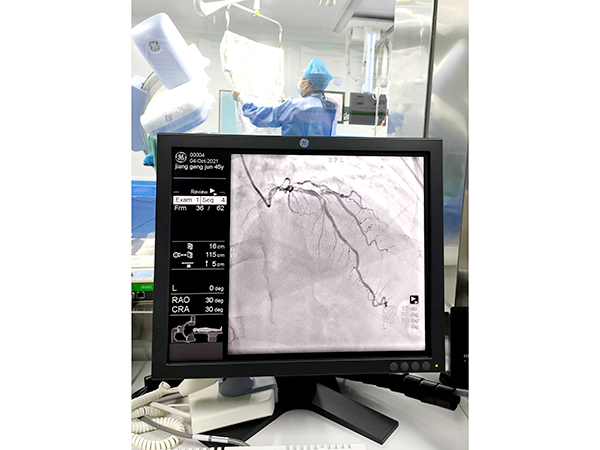

介入导管室(DSA)